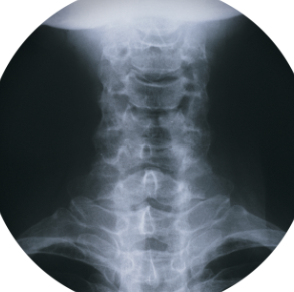

목 디스크에 좋은 운동에 대해 알아보도록 하겠습니다. 목디스크는 목의 디스크(물림판)가 손상되거나 이상을 가지고 있는 경우 발생하는 질환입니다. 목디스크는 디스크가 터져나올 수 있는 디스크 추간판 탈출증후군과는 다르며, 통증, 근육 약화, 마비 등의 증상을 나타냅니다. 목디스크는 외상, 나이, 체중 등이 원인이 될 수 있으며, 통증 완화를 위해 물리치료, 침술, 약물 치료 등의 치료법이 있습니다. 디스크 추간판 탈출증후군과는 달리 목디스크는 대개 치료로 완치될 수 있으며, 조기에 적절한 치료를 받으면 재발 가능성도 낮아집니다.